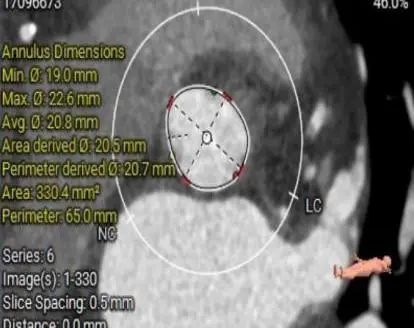

CT数据显示该患者为三叶瓣主动脉瓣。

主动脉瓣瓣环周长65.0mm,平均周长径 20.5mm,sov:25.7mm*27.1mm,瓣叶增厚,钙化主要分布于瓣叶,瓣环水平夹角51°。